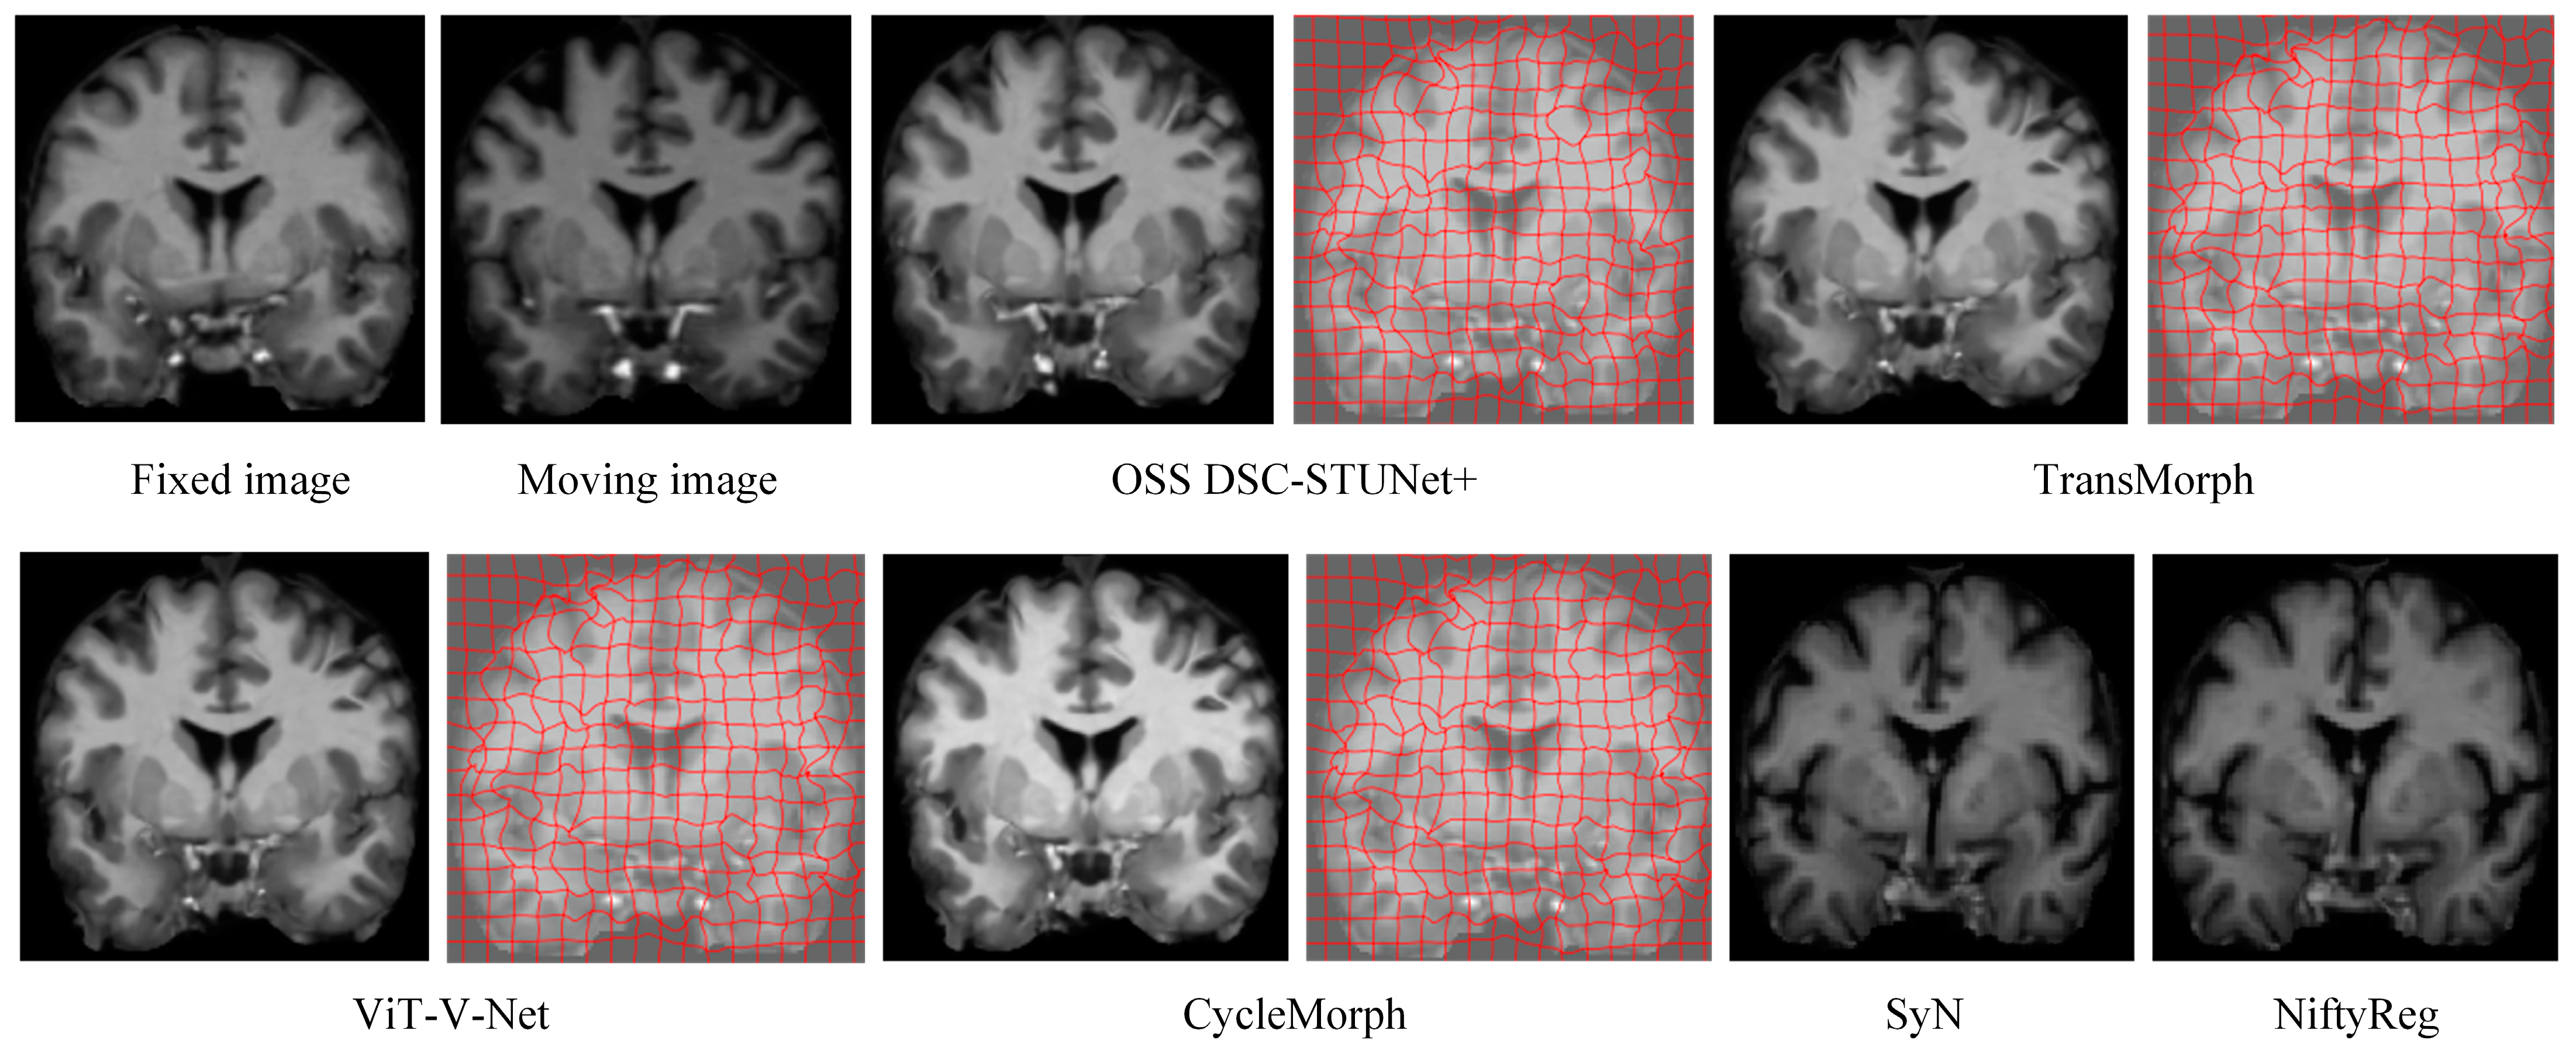

From Table 1, it can be observed that the proposed model achieved a Dice score on the IXI dataset that was 7.0% higher than CycleMorph, 6.6% higher than VoxelMorph, 16.3% higher than NiftyReg, 16.2% higher than SyN, 4.8% higher than ViT-V-Net, and 2.3% higher than TransMorph. From Table 2, the model’s Dice score on the OASIS dataset was 5.3% higher than CycleMorph, 4.8% higher than VoxelMorph, 9% higher than NiftyReg, 7.5% higher than SyN, 4.2% higher than ViT-V-Net, and 1.8% higher than TransMorph. From Table 3, on the LPBA40 dataset, the proposed model’s Dice score was 7% higher than CycleMorph, 5.9% higher than VoxelMorph, 1.1% higher than NiftyReg, 1.7% higher than SyN, 5.4% higher than ViT-V-Net, and 2.6% higher than TransMorph. Figure 7 and Figure 8 present the registration results of the different methods on the IXI dataset and OASIS dataset, respectively. From Figure 7 and Figure 8, it can be observed that the proposed method not only exceled in global accuracy compared to the conventional registration methods but also better preserved the details in the images.

The introduction of weakly supervised learning and optimization methods into the registration model resulted in a 0.7–4.1% increase in Dice score and reduced the percentage of non-diffeomorphic voxels (|Jφ| < 0) by half. This demonstrates that OSS not only improved the model performance but also prevented the generation of overly sharpened deformation fields, which can be visually observed by comparing the actual registration results in Figure 7. In the Figure 9, we illustrates the registration results, deformation fields, and deformation grids of the OSS DSC-STUNet+ model with the application of the weakly supervised optimization strategy, compared to the 3D DSC-STUNet+ model without the weakly supervised strategy. The figure shows that the optimized deformation field captured finer details, while preserving good local details, and the global registration performance was also partially improved.

Figure 7. Registration results and deformation fields of different methods on the IXI dataset (z = 124).

Figure 9. The registration results, deformation field, and deformation grid of the registration model before and after optimization.